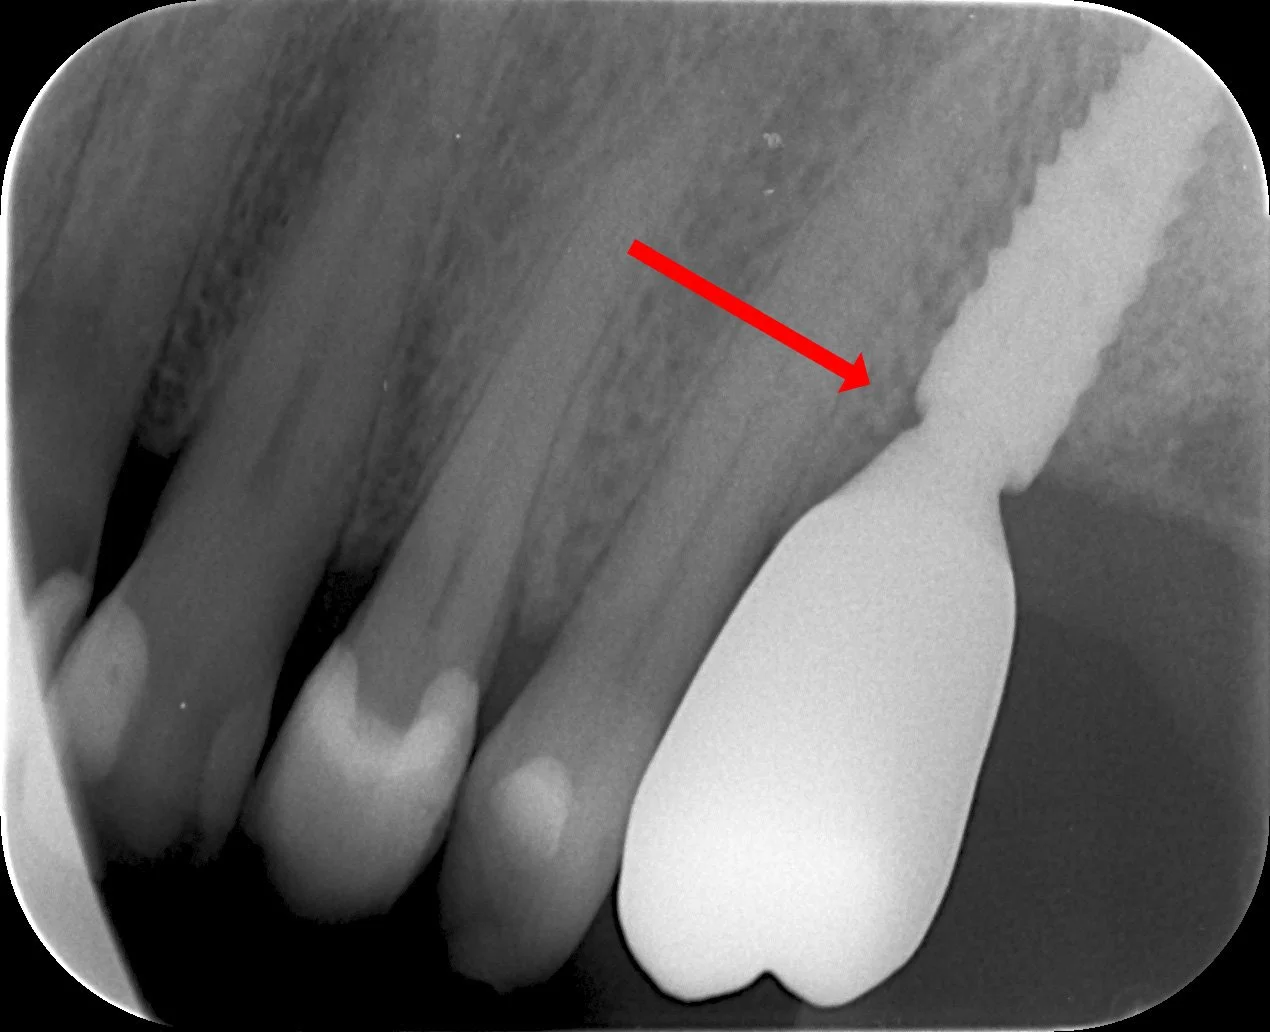

Jatke painaa distaalisesti ja aiheuttaa kipua potilaalle vuoden ajan

Kruunu irrotettu, jatke hiottu ja kiillotettu. Vaivat poistuneet.